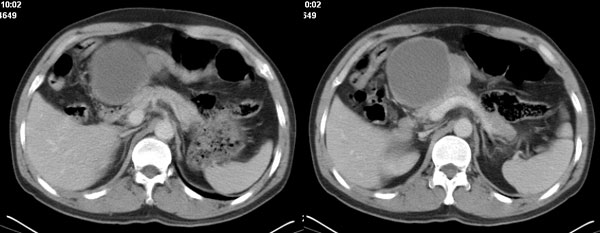

影像学表现:1 腹腔前中部、胰腺前方囊实性病灶(个人认为确定有否实性成分存在这是关键,涉及到鉴别诊断,如果是口服阳性造影剂则可明确左侧是不是小肠了),囊性部分囊壁不均,实性部分有强化,与小肠关系较密切,局部小肠受推移;与胰头、胃后壁均有脂肪间隙存在;2 胰腺无异常改变,胰周无渗出;3肝后段包膜下2个小圆形低密度灶,从图像和楼主提供的ct值来看有轻度强化,灶周无片状强化,不似单纯囊肿及肝癌、炎性病变表现;4 腹膜后及腹腔内无淋巴结肿大。

分析:1 如果腹腔内是囊实性病灶,则应多考虑肿瘤性病变,如源于小肠的间叶源性组织如神经源性肿瘤或间质瘤等;如果这么大存在恶性变的可能,那么肝内则可考虑为转移,征象亦符合;这种可能性最大;

诊断:小肠间叶组织源性肿瘤如神经源性肿瘤或间质瘤恶性变伴肝内转移可能性最大,不除外先天性胆管囊肿。

胰腺边界清晰,胰周筋膜不厚,胰周脂肪密度无明显增高;其前方囊实性病灶,边界清晰,增强后实性部分轻度强化;肝内多发边界清晰低密度影,增强后无明显强化(平扫ct值42.9,动脉期48.6,静脉期58.2,延迟期62.2)。

考虑:胰腺囊腺瘤,肝内小肝癌可能大。

我们先确定病变来源于何处。从片上看,应该说是起源于肠道的囊实性的肿块。二、肝内低密度影,增强强化随时间强化,考虑小血管瘤。